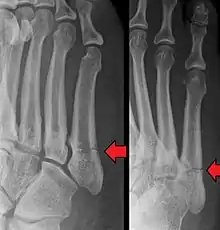

A fratura de Jones é uma fratura óssea entre a base e a parte do meio do quinto metatarso do pé,[1] que resulta em dor, perto da parte do meio de pé do lado de fora.[2] Pode existir também hematomas e dificuldade para andar.[3] O início geralmente é súbito.[4]

O diagnóstico é normalmente baseado na clínica (dor na lateral externa do pé e hematoma após trauma físico) e confirmado com radiografia.[3]